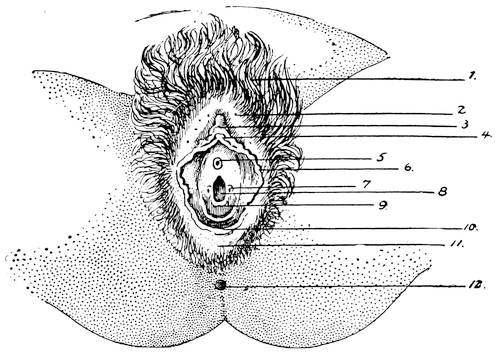

F. The Female External Genitals

In the female the vestibule, or the shallow depression which was formed through the breaking through of the urogenital membrane, remains open throughout life, and is termed the vestibule of the vulva. From the sides of the lower part of the sinus a pair of evaginations are formed and give rise to the Bartholinian glands. The vestibule being in fact the open sinus urogenitalis, the urethra and the vagina naturally have their orifices in the same.

The genital tubercle ceases to grow in the female and becomes the clitoris. The genital folds or the lips of the vestibule become prolonged and form the labia minora or the nymphae. The genital swelling increases in size through adipose and fibrous tissue. The part situated on the ventral side of the clitoris becomes the mons veneris, while the lateral parts are converted into the labia majora of the vulva.